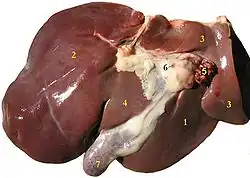

Le foie humain

Chez l'humain, il est impair et asymétrique. Il est logé dans l'hypocondre droit, la loge sous-phrénique droite, la partie supérieure du creux épigastrique puis atteint l'hypochondre gauche. C'est le plus volumineux des viscères abdominaux (2 % du poids corporel, soit une moyenne de 1 500 grammes pour une vingtaine de centimètres de long[1]) et l'organe du corps humain qui effectue le plus grand nombre de transformations chimiques. La discipline médicale qui lui est rattachée se nomme l'hépatologie. Le foie contient près de 13 % de la quantité de sang présent dans notre corps. Il peut connaitre des variations de volume allant jusqu'à 40 %[1].

Anatomie

On distingue habituellement deux faces au foie :

- une face diaphragmatique, lisse et en forme de dôme qui épouse la concavité du diaphragme ;

- une face viscérale, plane et présentant de nombreux replis de péritoine et des fissures.

En plus de ces deux lobes principaux, on distingue deux petits lobes à la face viscérale du foie : le lobe caudé et le lobe carré.

Face viscérale

La face viscérale du foie occupe la partie inférieure du foie, dans le plan transversal, et regard en arrière, en bas et à gauche. Elle présente deux fissures sagittales et une fissure transversale qui lie ces dernières et forme un « H » :

- la fissure sagittale droite (ou sillon sagittal droit) correspond à la fosse de la vésicule biliaire en avant, et au sillon de la veine cave inférieur en arrière ;

- la fissure sagittale gauche (ou sillon sagittal gauche) est le sillon continu formé par la fissure du ligament rond en avant, et par la fissure du ligament veineux en arrière. Le ligament rond du foie est le reliquat fibreux de la veine ombilicale, qui transporte le sang bien oxygéné et riche en nutriments, du placenta au fœtus. Le ligament veineux est également un vestige, du conduit veineux, qui court-circuite la circulation hépatique et achemine ainsi les nutriments du placenta à la circulation systémique. Lors de la naissance, ces deux veines s’oblitèrent en tissu fibreux (ligaments) ;

- le sillon transversal relie en arrière les deux sillons sagittaux et forme le hile du foie (ou porte du foie), point de passage des vaisseaux vasculaires et lymphatiques, des nerfs et des conduits biliaires.

C'est donc par la face viscérale que rentrent et sortent des structures telles que des vaisseaux sanguins et lymphatiques, nerfs et conduits biliaires, au niveau de la porte du foie (hile hépatique) : la porte du foie sert de porte de rentrée pour l'artère hépatique propre, la veine porte hépatique et les lymphonoeuds hépatiques, et de point de sortie pour les conduits biliaires (conduit hépatique commun et cystique, formant le cholédoque à la sortie du hile).

La face viscérale présente deux petits lobes accessoires : le lobe carré et le lobe caudé.

Lobes du foie

Le foie est divisé en deux lobes séparés par le ligament falciforme (ou ligament suspenseur)[8], le lobe droit (deux tiers du volume du foie) et le lobe gauche (un tiers du volume). On peut également individualiser deux autres lobes mineurs en taille : le lobe caudé (ou lobe de Spiegel) et le lobe carré[9].

Le lobe caudé, également appelé lobe de Spiegel, est visible à la partie postérieure de la face viscérale du foie, et est limité sur sa gauche par le sillon du ligament veineux (sillon sagittal gauche), sur sa droite par le sillon de la veine cave inférieure (sillon sagittal droit) et finalement en avant par le hile du foie. Il est nommé ainsi car il est muni d'un prolongement allongé en forme de queue, le processus caudé, qui rejoint le processus papillaire (faisant également partie du lobe caudé). Sur le plan anatomique comme fonctionnel, il est considéré comme un lobe individuel : sur le plan anatomique, grâce aux limites citées précédemment, et sur le plan fonctionnel, par l'apport vasculaire. Il est vascularisé par des vaisseaux afférents venant des foies droit et gauche (veines et artères caudées gauches et droites).

Le lobe carré du foie est visible est à la partie antérieure de la face viscérale du foie. Il est limite sur la gauche par le sillon du ligament rond (partie antérieure du sillon sagittale gauche), à droite par le fond de la vésicule biliaire (fundus) et en arrière par le hile du foie.